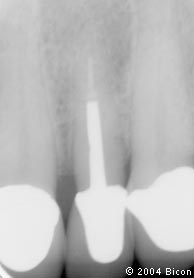

1. | 术前的X光片显示上颌左侧切牙的根管治疗失败。 |